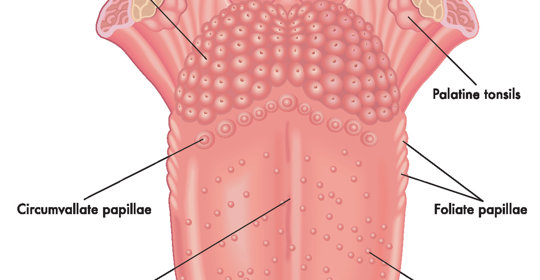

顱神經損害:舌下神經功能及損傷後果